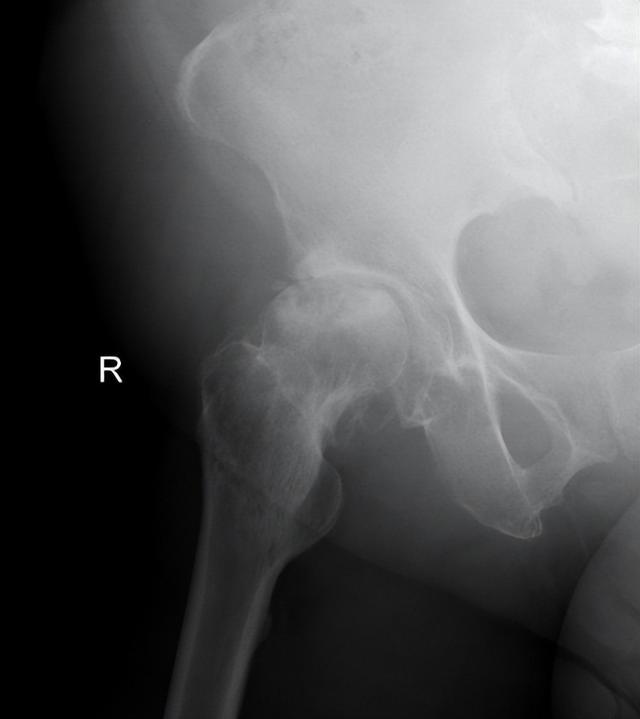

▲术前影像资料(股骨头塌陷、骨质增生)

经进一步影像学检查,接诊的柴志勇副主任医师发现,朱女士股骨头已经出现变形塌陷,髋关节周围出现大量的骨质增伤,关节僵硬,关节间隙狭窄,呈现出典型的股骨头坏死晚期影像学表现,唯有全髋关节置换才能解决他目前的问题。